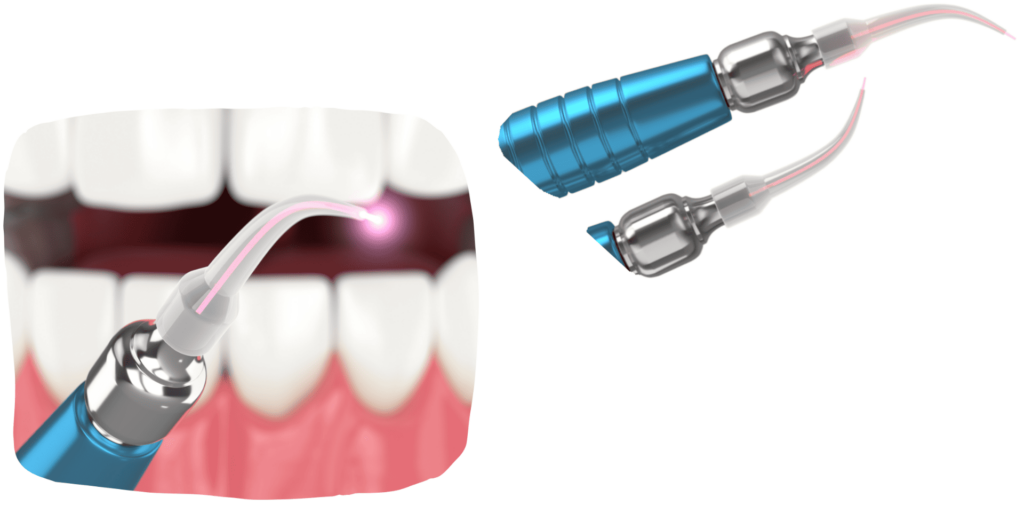

DENTALNI LASER

Primjenom lasera u oralnoj kirurgiji postižu se izuzetni rezultati jer omogućava preciznu obradu tkiva uz minimalno oštećenje okolnih struktura, značajno smanjuje postoperativnu bol i oticanje, ubrzava cijeljenje i regeneraciju tkiva te smanjuje rizik od infekcija zahvaljujući svom antibakterijskom djelovanju.

Laser značajno poboljšava sigurnost i uspješnost oralno-kirurških zahvata.

Laser značajno poboljšava sigurnost i uspješnost oralno-kirurških zahvata.